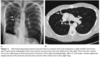

What is the aortopulmonary window?

- space under the aortic arch and above the left pulmonary artery